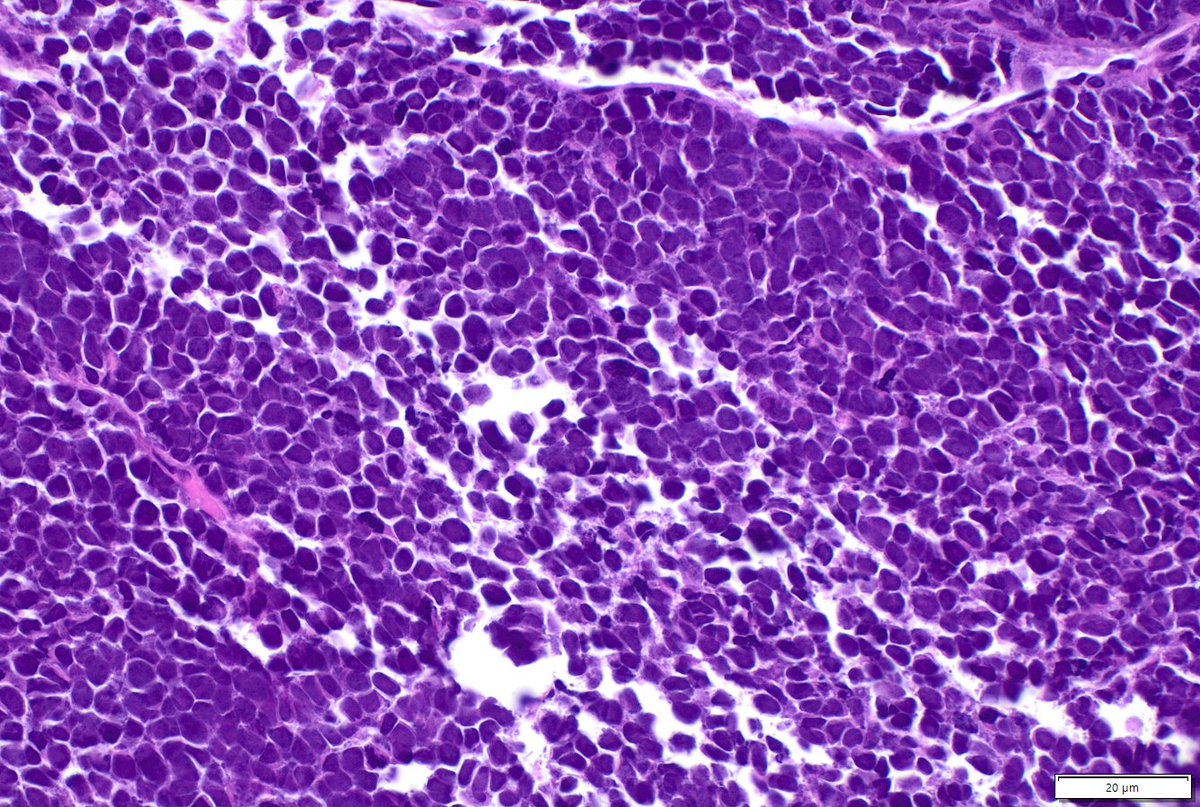

Great time showcasing our work comparing FNA vs FNB for serous cystadenomas during the Stowell-Orbinson session at #USCAP2026. Thankful for my great mentors (Dr. Centeno & Dr. Tabbara) from @MoffittNews & @USFpathology 🤩 bonus: characterizing tp53 mutations in MDS! #uscap26